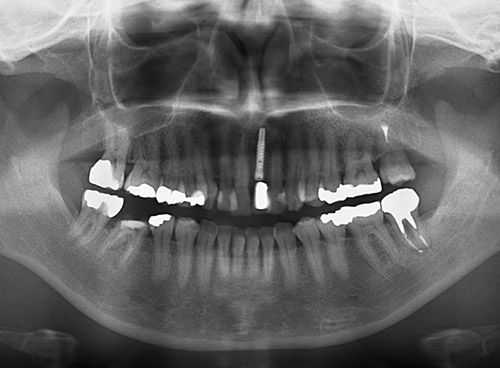

図13 埋入直後パノラマX線像。 -